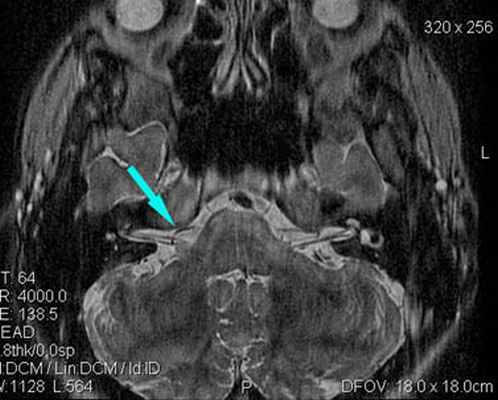

(Слева) При аксиальной МРТ CISS у пациента с левосторонним гемифациальным спазмом визуализируется петля левой позвоночной артерии, выдающаяся в цистерну ММУ, где она воздействует на проксимальную часть лицевого нерва в области выхода корешка.

Определяется близкое расположение артериального сосуда и лицевого нерва (указано стрелкой), что может являться причиной гемифациального спазма

Определяются признаки компрессии лицевого нерва около ствола головного мозга крупным артериальным сосудом – позвоночной артерией (указано стрелкой).